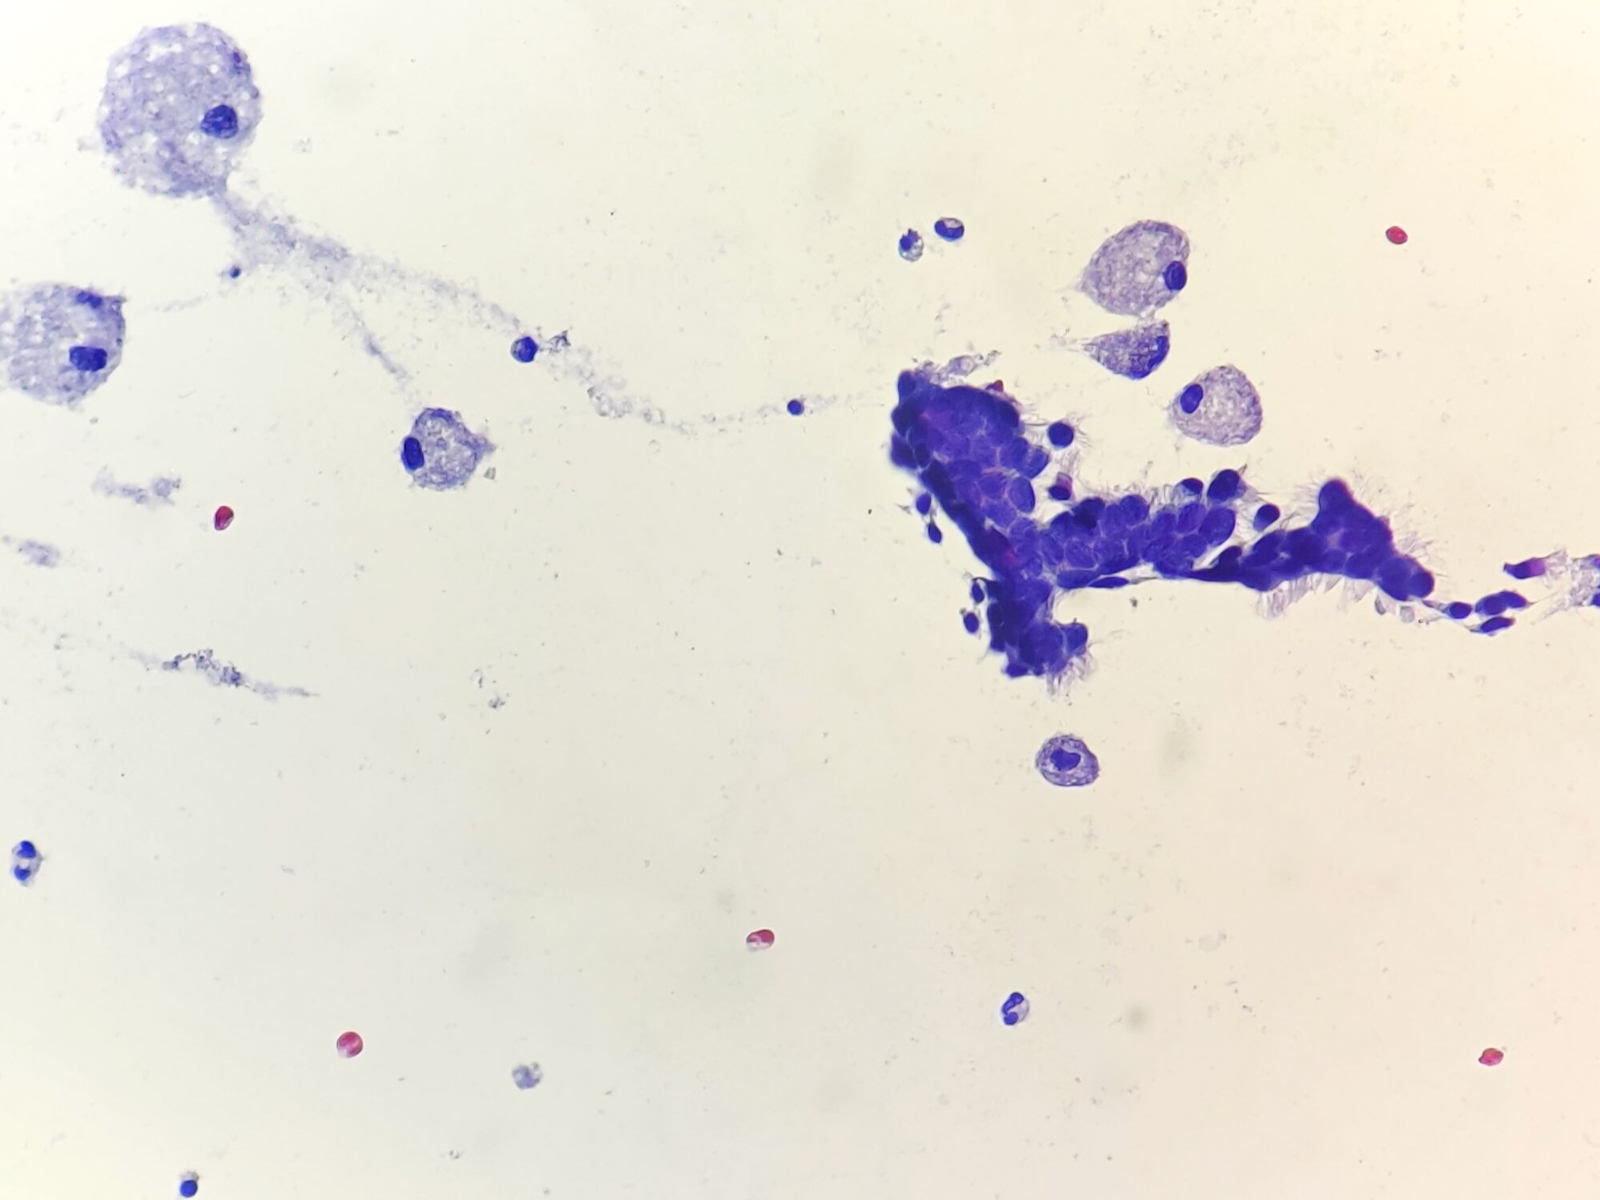

Cytology description

- Preoperative FNA is moderately sensitive but with many false negatives (Diagn Cytopathol 2005;33:365)

- FNA smears are of low cellularity, with predominant inflammatory cells outnumbering epithelial cells, similar to branchial cleft cyst:

- Macrophages, either foamy or hemosiderin laden

- Mature lymphocytes and neutrophils (predominantly if the cyst is infected)

- Squamous or ciliated columnar epithelium

- Colloid is common, ranging from thick and fragmented to thin and watery

- Admixture of cholesterol crystals

- Thyroid tissue found in < 10% of aspirates, likely due to deep embedding in the cyst wall

Cytology images

Contributed by Andrey Bychkov, M.D., Ph.D., Ayana Suzuki, C.T., Ram Kumar Kurpad R, M.B.B.S., M.D. and Y. C. Spoorthy Rekha, M.B.B.S., M.D.

Images hosted on other servers: